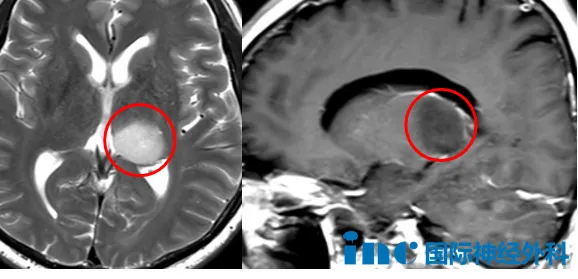

2025年4月体检发现颅内占位病变,伴有记忆力减退症状。影像学检查显示左侧丘脑-海马尾部存在23×19×20mm占位,考虑低级别胶质瘤可能性大,医院建议手术治疗。患者因顾虑开颅手术风险,转而尝试中药调理,初期自觉记忆力有所改善。

然而8个月后复查显示病灶增大至24×20×25mm。肿瘤的持续生长使手术决策再次成为焦点问题。患者主要担忧包括:开颅手术风险程度、偏瘫可能性以及是否可继续保守治疗。最终决定向德国巴特朗菲教授咨询专业意见。

巴教授评估后指出,虽然影像学特征倾向于低级别胶质瘤,但病灶内出现强化信号提示存在恶性转化风险,不建议继续等待观察。手术治疗既可明确病理诊断,又能实现最大程度肿瘤切除。早期手术干预相比出现严重症状后再手术,恢复效果更优。针对手术风险,教授详细分析指出肿瘤位于丘脑区域,术后存在右侧运动功能受影响的风险,但发生率较低。他还分享了近期在苏州完成的类似部位手术案例,患儿术后未出现偏瘫并发症,这为患者增强了信心。王先生决定寻求巴教授在华期间的示范手术机会。